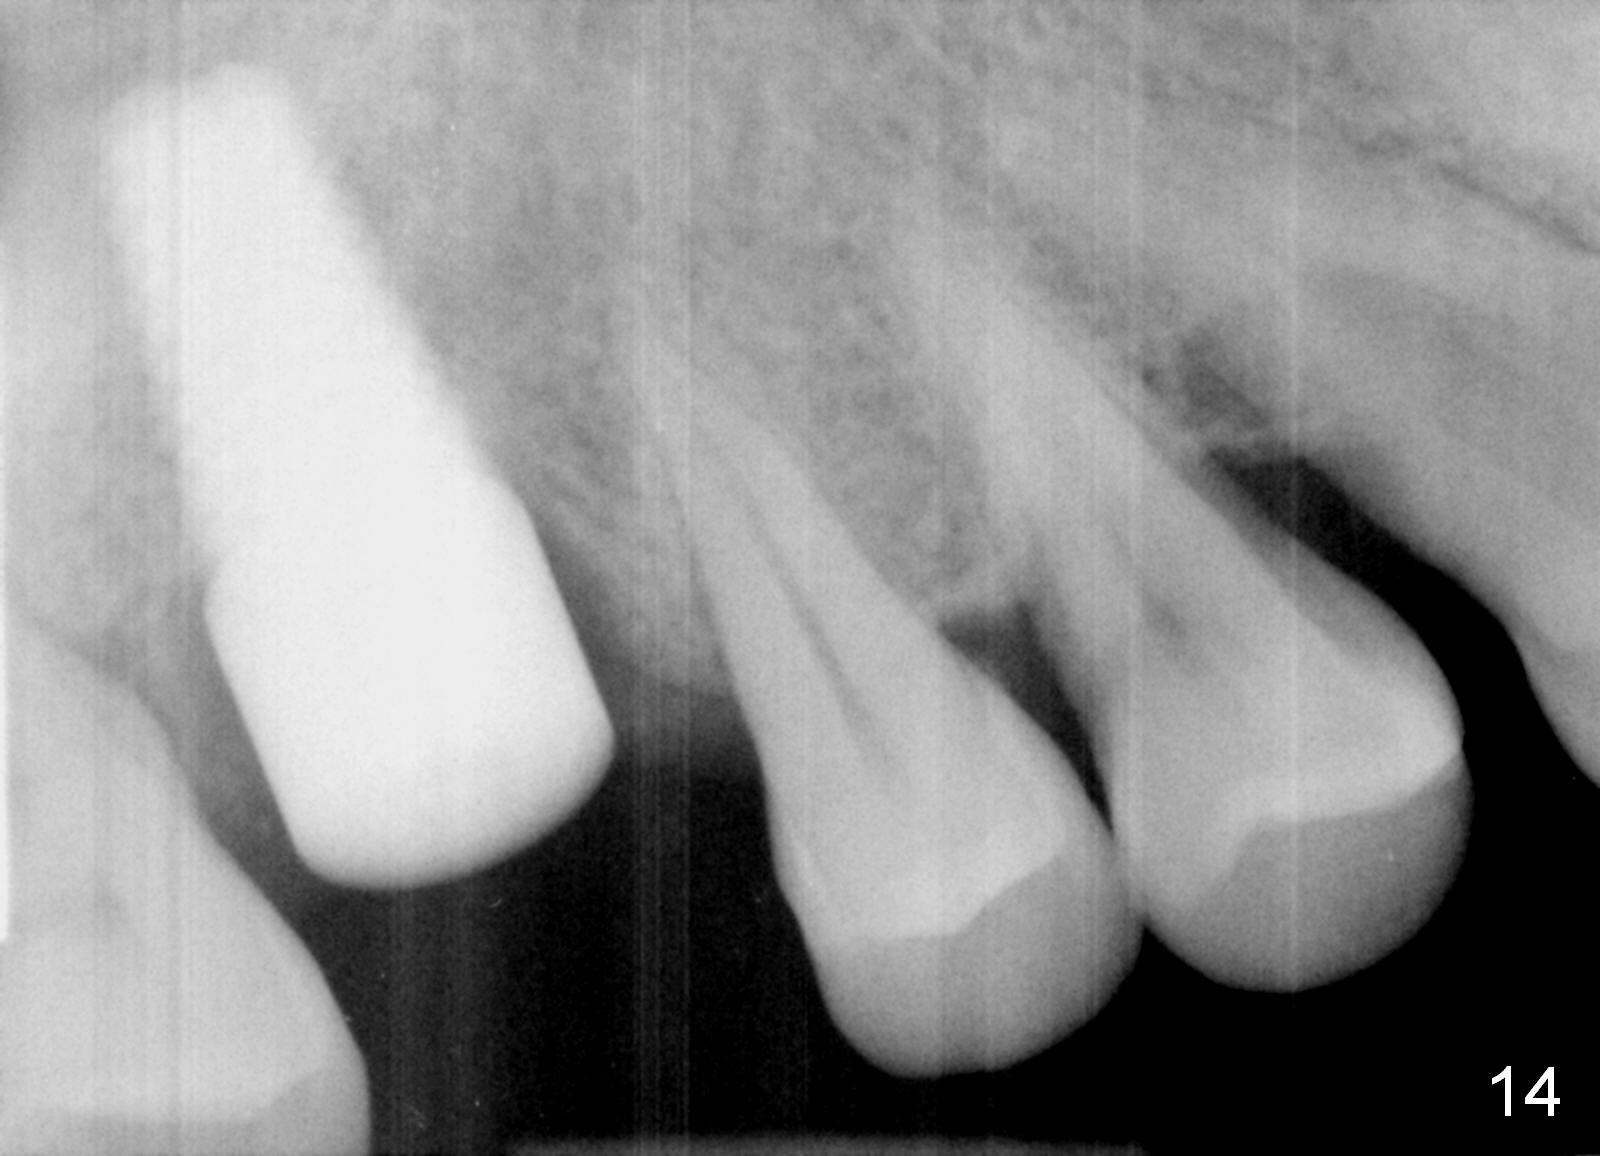

The patient returns for restoration 23 months postop; the implant appears to have been osteointegrated (Fig.14). There is no buccal or palatal gingival recession. The large implant appears to close the large defect readily and enhances bone/implant contact. The buccal plate seems to be thin 3 years post cementation, although there is no sign of periimplantitis (Fig.15). The mesial papilla is severely recessive with open contact 3 years 5 months post cementation. BW shows DO caries of the teeth #2, 4 and 30. The crown is removed for better oral hygiene by fabricating a provisional and conservative composite for #4. Water Pik is recommended.

14